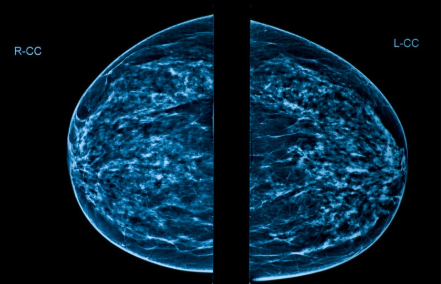

การบริการตรวจแมมโมแกรม เป็นการตรวจหาความผิดปกติบริเวณเนื้อของเต้านมด้วยเครื่องแมมโมแกรม ซึ่งเป็นการตรวจทางรังสีชนิดพิเศษ สามารถคัดกรองดูมะเร็งเต้านมได้ตั้งแต่ระยะเริ่มแรกและเป็นวิธีที่ดีที่สุดในการคัดกรองมะเร็งเต้านม วิธีนี้เป็นการตรวจที่แม่นยำ สามารถดูคราบหินปูน ถุงน้ำ หรือก้อนเนื้อที่เต้านมได้ตั้งแต่ระยะเริ่มแรก ใช้เวลาตรวจเพียง 30 นาที และไม่ต้องงดน้ำและอาหาร เนื่องจากเนื้อเยื่อภายในเต้านมของผู้หญิงมีความหนาแน่นที่แตกต่างกัน คนที่เนื้อเต้านมหนาแน่นมาก อาจทำให้บดบังก้อนมะเร็งหรือมองเห็นผิดพลาด แพทย์จึงมักแนะนำให้มีการตรวจด้วยวิธีการอัลตราซาวนด์ควบคู่กับแมมโมแกรม

• การตรวจแมมโมแกรมสำหรับคนทั่วไป แนะนำให้ทำเมื่ออายุ 40 ปีขึ้นไป โดยทำปีละครั้ง แต่ในกรณีที่มีความเสี่ยงสูง เช่น มีกรรมพันธุ์มะเร็งเต้านมในครอบครัว ควรเริ่มต้นค้นหาเร็วกว่าปกติ 5-10 ปี